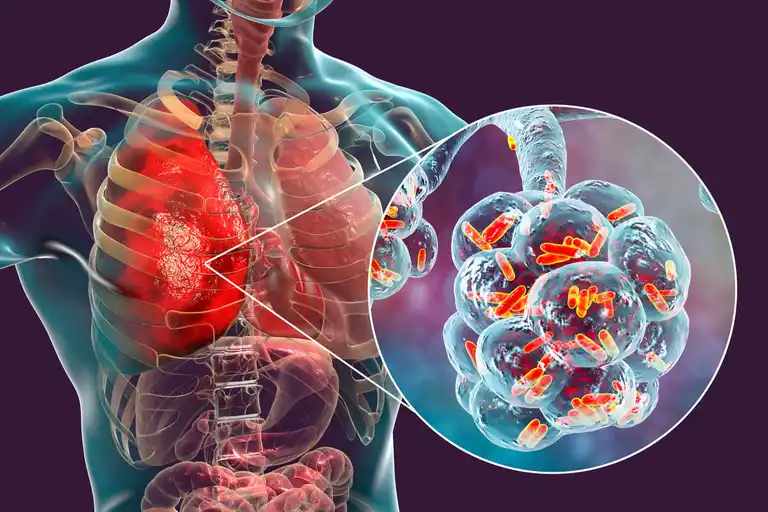

폐 반점의 원인과 치료

흉부 엑스레이 검사에서 폐에 반점이 생긴 것처럼 보이는 이유는 무엇일까? 이 글에서 자세히 알아보자.

흉부 엑스레이는 폐 질환을 확인할 때 가장 흔히 사용되는 영상 진단법이다. 하지만 흉부 엑스레이 검사에서 폐에 희끄무레한 반점이 생긴 것처럼 보이는 이유는 무엇일까? 지금부터 폐 반점의 원인과 치료를 자세히 알아보자.

폐렴과 기관지 폐렴

폐 조직의 감염은 폐렴이지만, 공기가 폐로 들어갈 수 있도록 하는 기관지에 감염이 생긴 상태는 기관지 폐렴이라고 한다. 폐렴의 원인으로는 바이러스, 박테리아, 곰팡이 등이 있다.